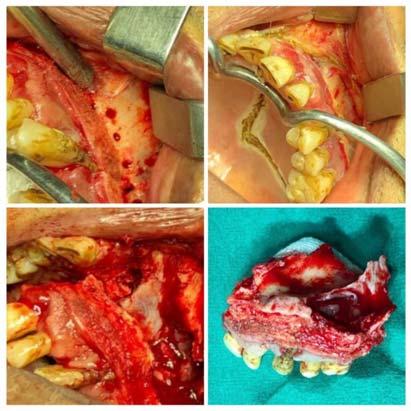

Once Mucormycosis was confirmed, within 72 hours, surgery was performed as well (Fig 2). Post surgery, either Amphotericin B therapy was instituted if it was available and if it was not available then either orally Posaconazole (200 mg q8h) was administered or Isavuconazole at a loading dose of 372 mg orally every 8 hours and maintenance dose of 372mg orally once a day. Inj Amphotericin B was administered at 35 mg/kg. Daily renal function tests had to be performed due to possible nephrotoxicity of Amphoterecin B. Those who could afford, liposomal Amphotericin B injections were given which had lesser renal complications. Alteration in dosage was adjusted according to renal tolerance. Amphotericin B was not available in private clinic/hospitals but only available in government hospitals. Those who were ready to get

Fig 2 — Collage representing resection with debridement of the maxillary lesion and lastly providing an obturator